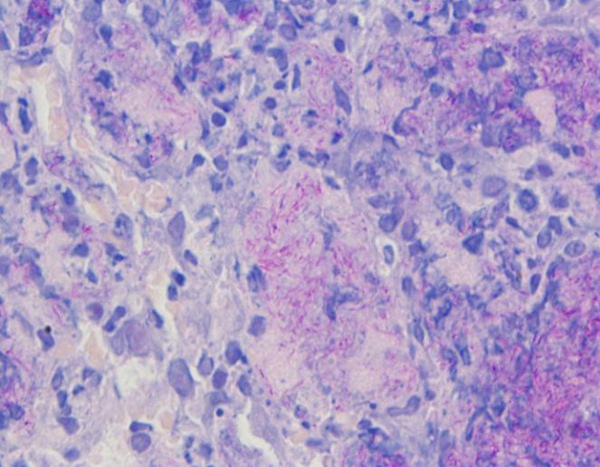

Ovaj set otopina za bojenje otpornih na kiseline prikladan je za otkrivanje bakterija otpornih na kiseline u tkivima. Nakon bojenja, jezgre su bile plave, a kiselootporne bakterije ljubičasto crvene.

Bakterije otporne na kiselinu su ljubičastocrvene s plavim jezgrama.